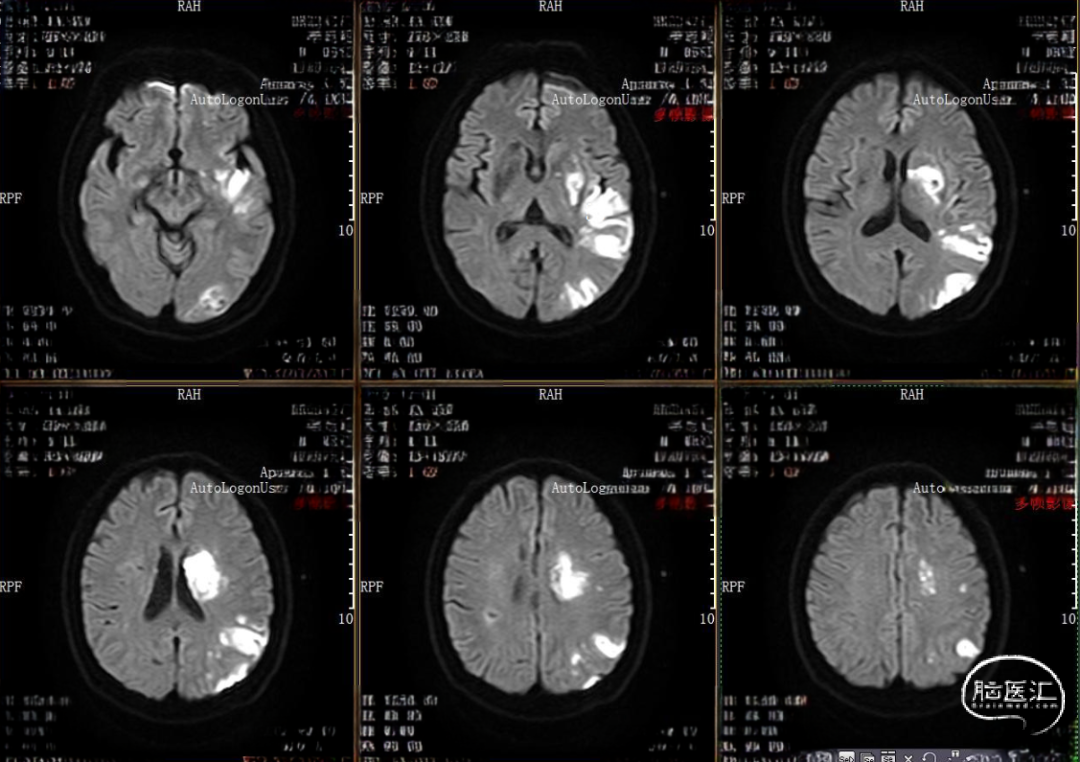

现病史:患者于7.5小时前突然出现右侧肢体乏力伴失语,就诊当地医院,查头颅MRI提示左侧大脑半球多发局部脑组织弥散受限,具体不详,症状波动进展,转来我院急诊。(当地未溶栓)

入院查体:意识模糊,失语,双侧向左凝视,右侧鼻唇沟变浅,伸舌不合作,口角向左歪斜,右侧肢体刺痛未见活动,NIHSS评分20分。

rCBF<30%:25.1ml

Tmax>6.0s:173.9ml

失配体积:148.8ml

术后MRI